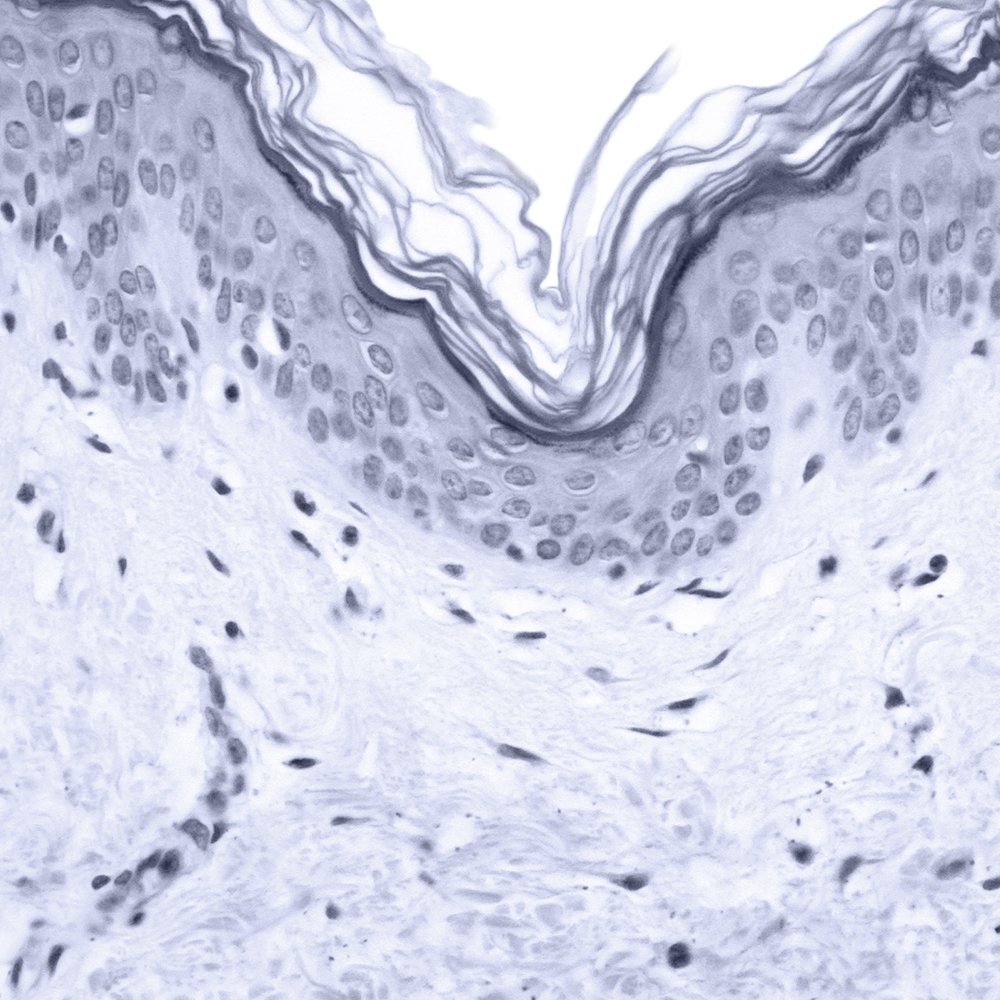

QUELLES SONT LES CARACTÉRISTIQUES D’UNE PEAU MATURE ?

Avec le temps, la peau s’affine et le processus de renouvellement cellulaire ralentit. On observe une sécheresse et un relâchement cutané plus ou moins prononcés. Plus fragile, la peau est davantage vulnérable face aux agressions extérieures, comme l’exposition solaire. Des marques et des taches brunes caractéristiques peuvent alors apparaître.

Aux coins des yeux, autour du nez et sur le front, les rides et ridules s’installent durablement et commencent même à se creuser, en raison de la sécheresse cutanée . Le teint manque de vitalité et des poches se forment sous les yeux. Cependant, les signes de l’âge peuvent être visiblement atténués grâce à un programme de soins adapté, reposant sur des principes actifs ciblés pour répondre aux préoccupations des peaux matures.